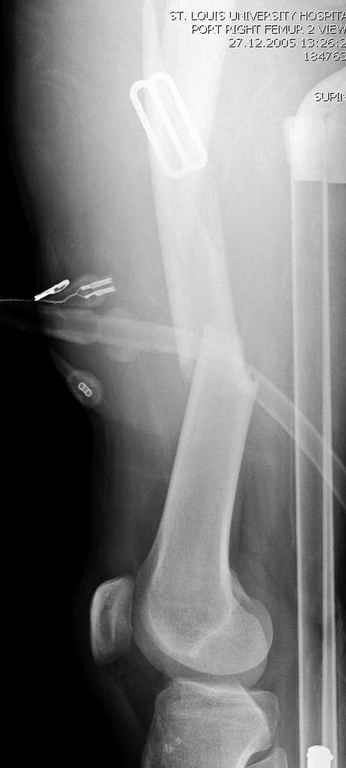

Здесь слайды случая больного с политравмой, включающей сегментарный перелом бедра и повреждение таза с нарушением тазового кольца, разрыв симфиза и перелома крестца зон 2 и 3.

На множественных слайдах важные моменты операции. Хотел бы подчеркнуть, как важно иметь возможности всех необходимых ренгенограмм, включая компютерную томографию и стандартных внутритазовых рентгенограмм (инлет и оутлет).